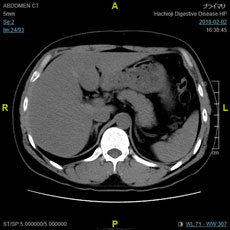

放射線科